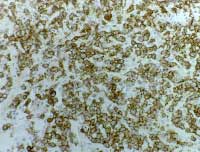

IMMUNOHISTOCHEMICAL

TECHNIQUES

![]()

ENLARGE

Demonstrated a strong positive staining for the CD30